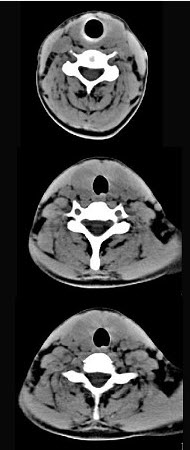

40岁,女性患者,双侧甲状腺肿大,CT扫描如图所示,请选择最佳答案()。

A、弥漫性甲状腺肿

B、甲状腺癌

C、甲状腺炎(桥本)

D、亚急性甲状腺炎

E、甲状腺瘤

C